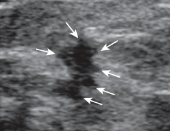

Hypoechoic intraductal mass

Microlobulations (1-2mm)

Calcificaitons